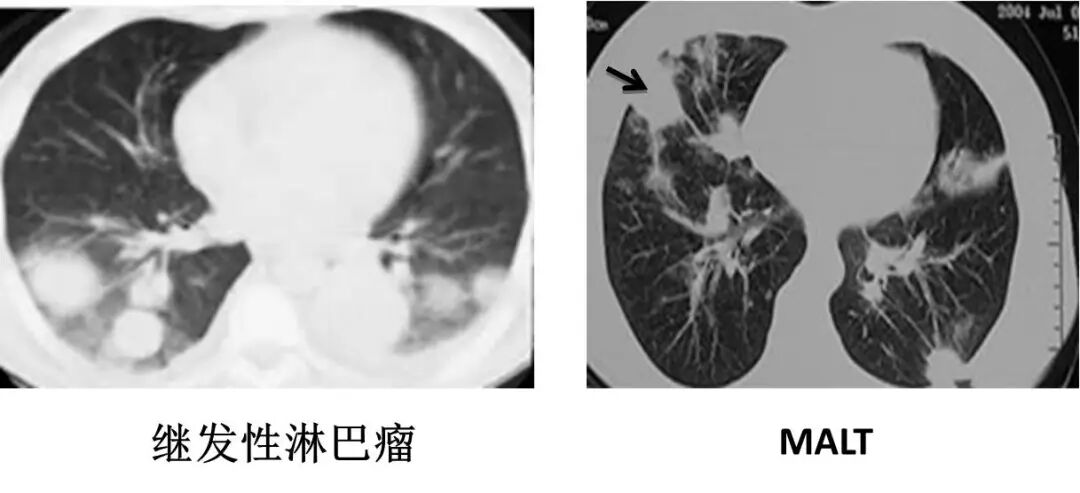

▼继发性肺淋巴瘤

继发性肺淋巴瘤

肺内网状结节性病变

多有胸外淋巴瘤病史,纵隔淋巴结肿大

▼支气管肺癌

支气管肺癌

▶肺内单发结节或肿块

▶多伴有纵隔、肺门淋巴结肿大

▶可见支气管阻塞

▶充气支气管管径正常,管壁破坏

肺粘膜相关淋巴瘤

结节、肿块,边缘模糊

充气支气管粗大、扭曲